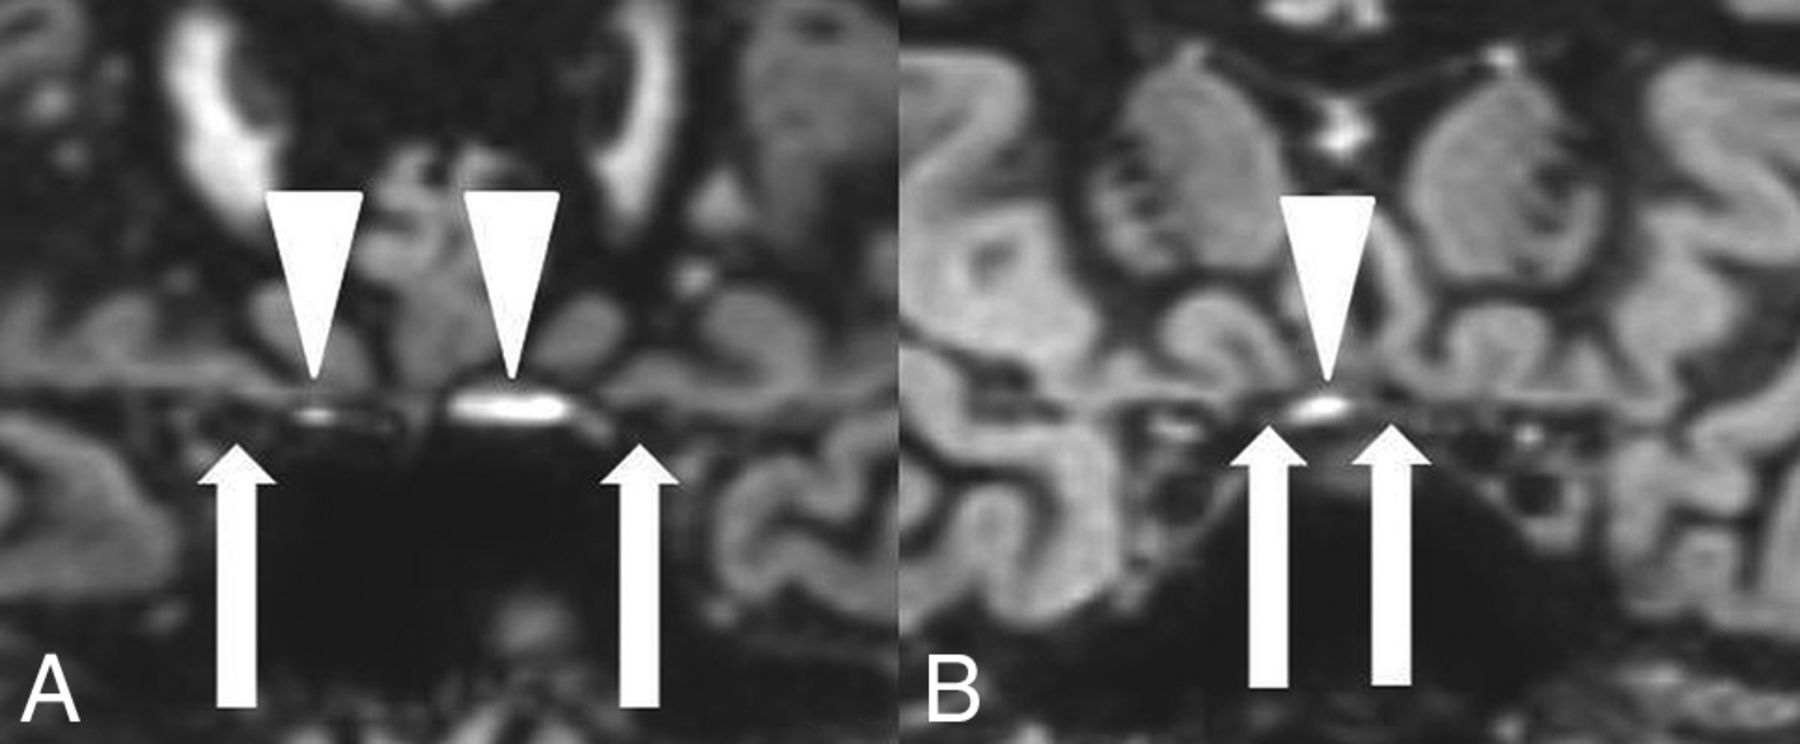

Hyperintense susceptibility artifacts (white arrowheads) at the air-bone interface next to the canalicular nerve segments (A) and next to the prechiasmatic nerve segments (B). Optic nerve segments are marked with white arrows.